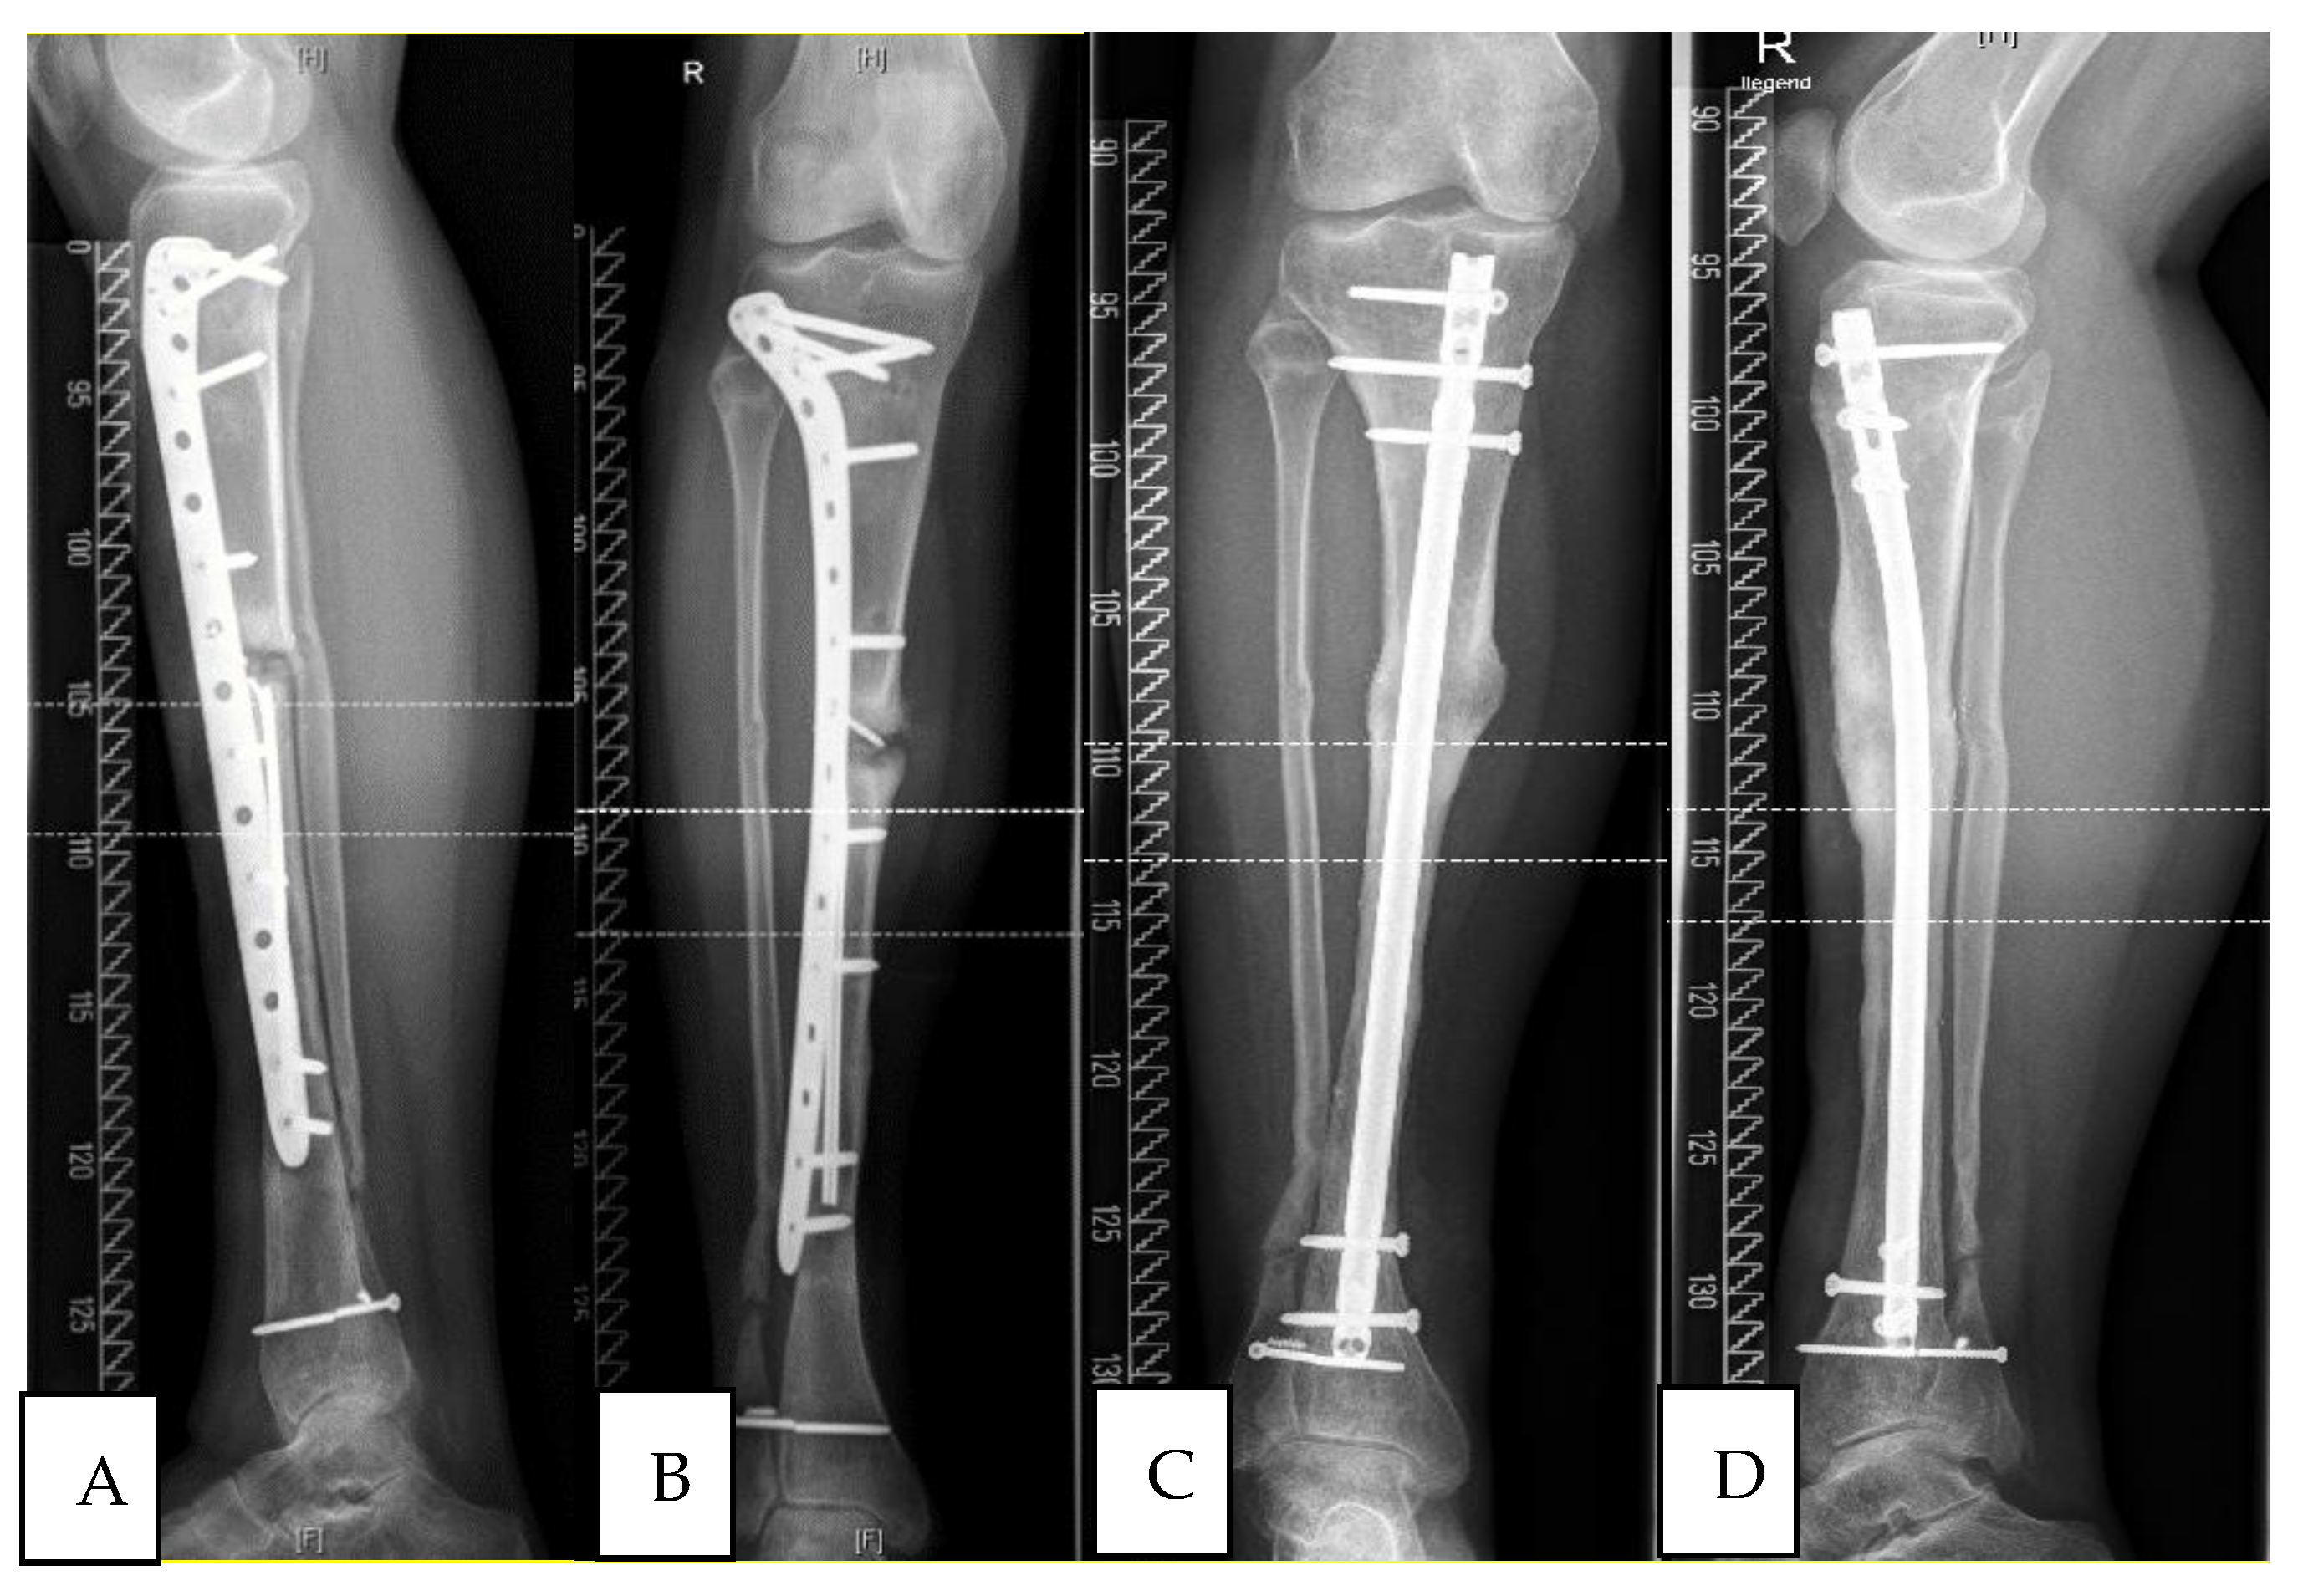

3.1. Study Group 1: Responders

3.2. Study Group 2: Non-Responder